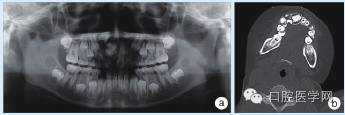

术后1年,11牙正常萌出(图3)。

图3 病例2术后1年全颌曲面断层片